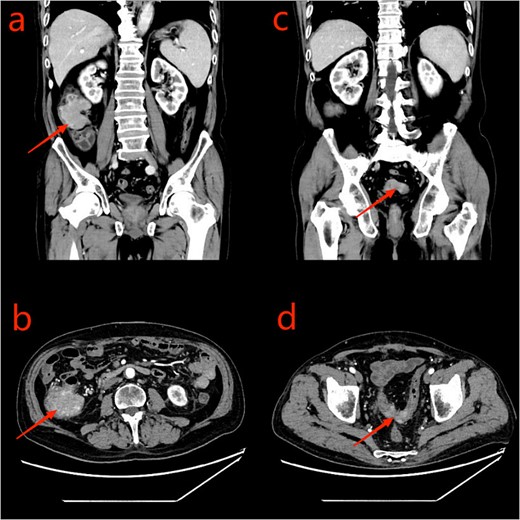

A 75-year-old male patient was admitted to the Department of Hematology due to small B-cell lymphoma. The patient had been experiencing incomplete intestinal obstruction for nearly 1 year and had been self-medicating with diarrhea-inducing medication obtained outside the hospital. During hospitalization, the patient exhibited a marked decline in appetite, accompanied by cessation of bowel movements, nausea, and vomiting. The patient weighed 85 kg, stood at 1.68 m tall, and had a body mass index of 30.12 kg/m2. He had no history of smoking, alcohol consumption, or surgery. Physical examination: the patient’s body temperature, heart rate, and blood pressure were normal, with abdominal distension, scattered abdominal tenderness without obvious rebound pain, and drumming sound on abdominal percussion. Laboratory tests: platelets, tumor markers CEA, the rest showed no abnormality. Chest computed tomography (CT) showed a few infection foci in the lungs, with no metastatic foci observed. Enhanced CT scanning of the abdomen revealed tumors in the sigmoid and ascending colon, with significant thickening observed in the proximal sigmoid colon tumor (Fig. 1). Colonoscopy revealed complete obstruction of the sigmoid colon (Fig. 2).

CT scan of the abdomen and pelvis: a: ascending colon tumor (coronal scan); b: cecum tumor (axial scan); c: sigmoid tumor (coronal scan); d: sigmoid tumor (axial scan).